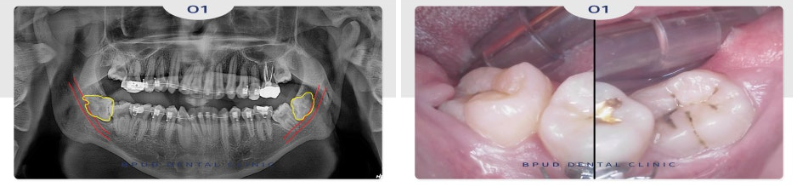

24.12.03

완전 매복 고난이도 사랑니로

신경에 완전히 닿아 있어 신경 손상의

위험이 높은 케이스였으나 문제없이

발치 계획을 수립하였습니다.

이처럼 정상적인 발치를 할 수 없는

위치에 치아가 있는 경우 발치 시

어려움이 있기 때문에

3D CT 촬영을 통해 정밀한 진단을

바탕으로 치아 상태를 입체적으로 파악하여

계획을 세워야 부작용의 위험을 줄일 수 있습니다.

양쪽의 사랑니를 모두 쪼개어

발치를 한 모습입니다.